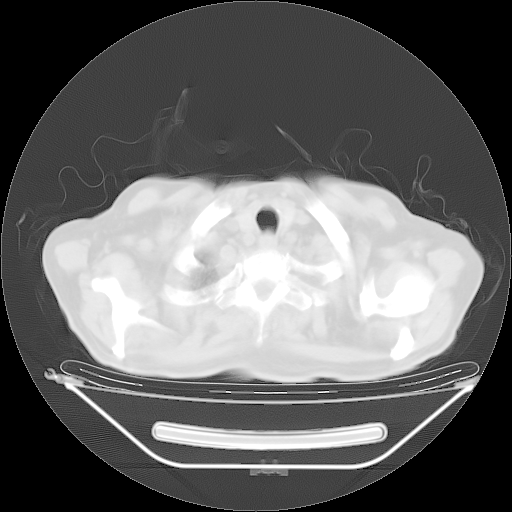

胸腹部CT,诊断意见:左上肺叶钙化灶、左侧胸膜局限性增厚并钙化、胆囊炎。描述部分肺组织呈磨玻璃样改变。